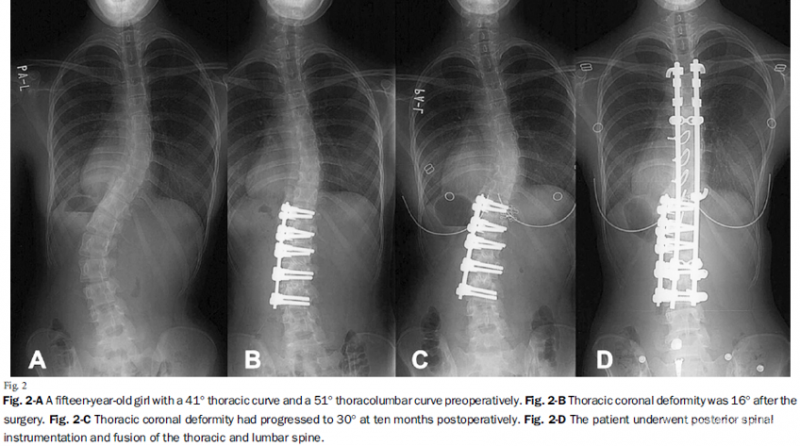

4.在胸腰段/腰段选择性融合矫正后,胸段弯曲并非都能获得良好的代偿矫正。对于胸段弯曲>40°,且胸腰段/腰段弯曲与胸段弯曲之比<1.25的患者,应行后路手术融合双弯,以避免单纯前路矫形术后胸弯失代偿。

图8.胸弯>40°、胸腰段弯曲与胸段弯曲之比=1.24(<1.25)术后胸弯失代偿

为了比较Lenke 5C型脊柱侧凸前路手术和后路手术的疗效,Firoz M.等人[5]对161例Lenke 5C曲线患者进行了一项随访2年的前瞻性研究。这些患者分别接受前路双棒系统(69例)或后路椎弓根钉系统(92例)矫形手术。对两种方法进行术前和术后2年的影像学资料、SRS结果评分和围手术期比较。

结果显示在末次随访矫正率上前路组(59.1%)与后路组(59.3%)之间无统计学差异(P=0.940),且两组患者平均住院时长相似(前路5.6天,后路5.7天)、2年随访期间SRS问卷评分无明显差异。相较于后路组,前路手术平均可节约1.6个融合节段(P<0.001),但通过后路手术可以恢复更理想的腰椎前凸(P<0.001)。